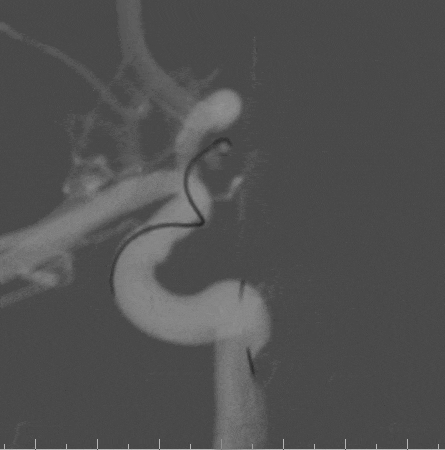

术前影像

栓塞过程

Tethys®中间导引导管和Presgo®微导丝、微导管到位后,先行动脉瘤前下方瘤囊栓塞,陆续填入两枚Jasper®SS弹簧圈,最后行瘤颈填塞,以Jasper®SS弹簧圈收尾,完成瘤腔及瘤颈致密填塞。

术后即刻影像

本例病例为后交通动脉微小动脉瘤,使用Jasper®SS弹簧圈进行填塞和收尾,填塞过程较为稳定,圈体非常柔软,钻空能力强,分布较为均匀,收尾时可以有效覆盖瘤颈,达到致密填塞效果。